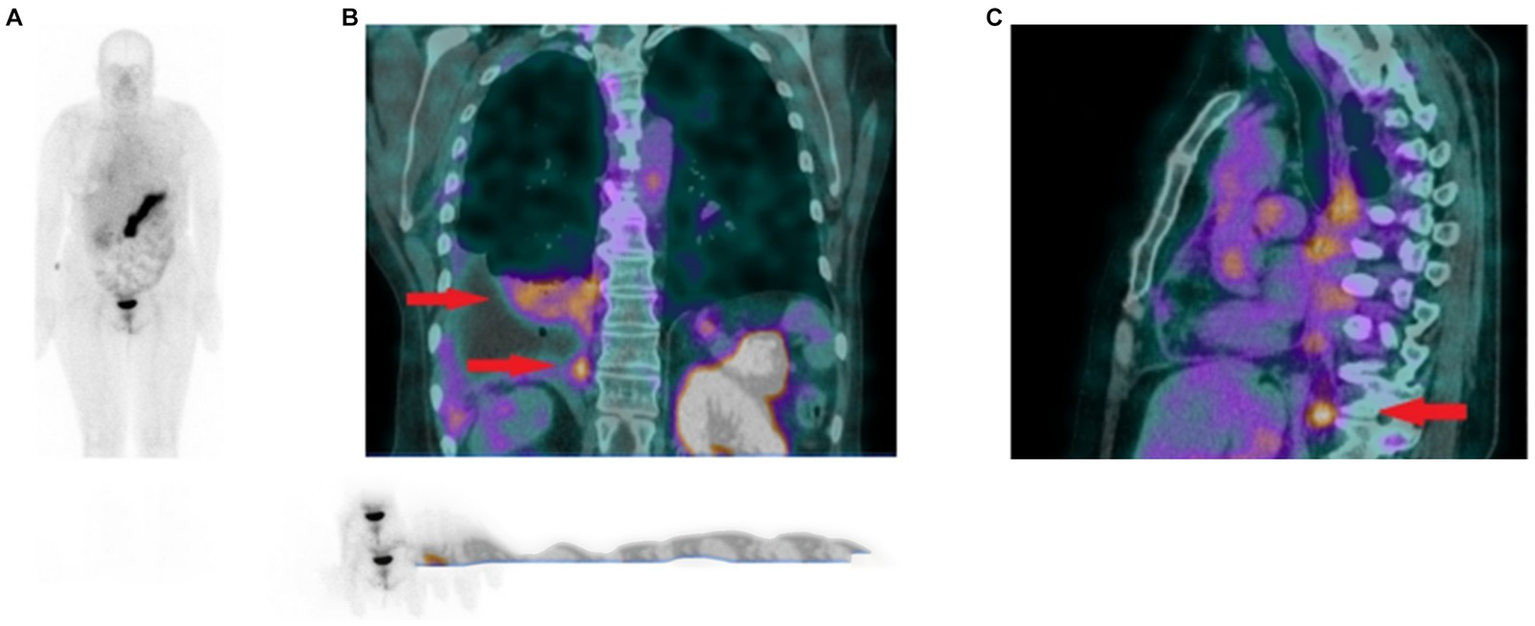

In 2021, the GRPR-targeting radioantagonist [99mTc]Tc-DB15 (Figure 6, 9) showed promising results in a pilot translational study in two advanced BC patients. The tracer allowed the visualization, by SPECT/CT imaging, of disseminated bone metastasis, soft tissues metastasis and lymph nodes that warrant further investigations, as shown in Figure 10 (90).

Figure 10

(A) Whole body scan obtained 3 h after injection of [99mTc]Tc-DB15 in the anterior projection shows physiological accumulation in the pancreas and increased uptake in the right pleura. (B) SPECT/CT coronal image of the chest presenting increased tracer uptake in the metastatic infiltrations in the pleura and lung parenchyma (red arrows). (C) SPECT/CT sagittal image of the chest depicting increased radioactivity accumulation in an enlarged (metastatic) phrenic lymph node (red arrow). Adapted from [99mTc]Tc-DB15 in GRPR-Targeted Tumor Imaging with SPECT: From Preclinical Evaluation to the First Clinical Outcomes by Nock et al. (90), under Creative Commons Attribution (CC BY) license.